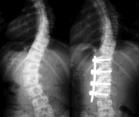

一种脊柱结构性的侧弯,生长发育期间原因不清楚的脊柱侧凸称为特发性脊柱侧凸。60%~80%的病例发生在女孩中.10~16岁儿童中有2%~3%可察觉到脊柱侧凸.当一侧肩胛似乎比另一侧高时,或衣服不能拉直时可能会首次怀疑到有脊柱侧凸,但更多的是在体格检查中查出的.最早的主述可能是长时间坐或站后腰部无力.随后是紧张区域的背部肌肉性疼痛,例如腰骶角.疼痛在青春期的特发性脊柱侧凸中不常见,因此需要进一步的检查。

根据年龄特点一般将特发性脊柱侧凸分为三种类型:幼儿型(0~3岁);少年型(4~9岁);青春型(10~16岁)。按脊柱侧凸顶椎所在的解剖位置又分为:①颈弯:顶椎在C1~C6之间。②颈胸弯:顶椎在C7~T1之间。③胸弯:顶椎在T2~T11之间。④胸腰弯:顶椎在T12~L1之间。⑤腰弯:顶椎在L2~L4之间。⑥腰骶弯:顶椎在L5或S1。